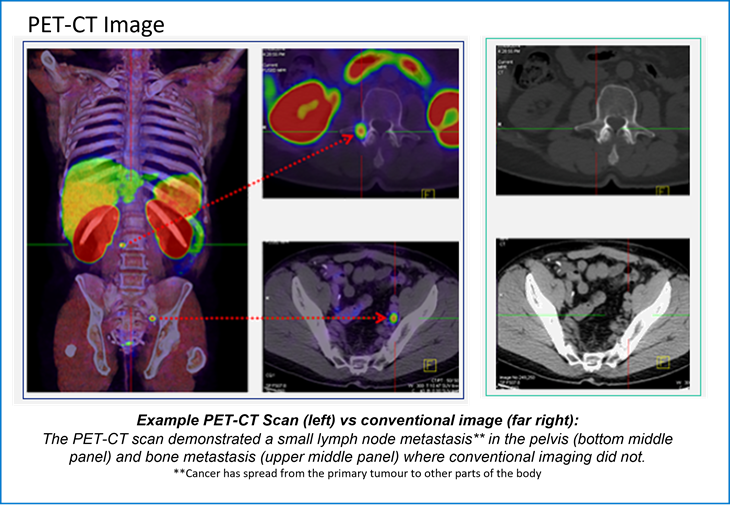

The PET-CT images